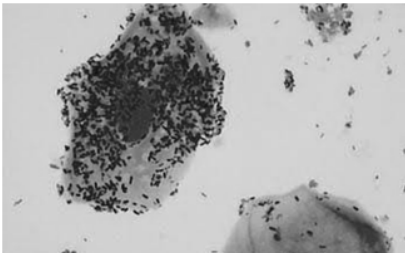

Uma gestante com dezesseis semanas e quatro dias compareceu ao pronto-atendimento com queixa de “corrimento vaginal” há quatro dias. O teste das aminas foi positivo e o exame especular é ilustrado na figura 1. Após a realização de coloração Gram, o resultado pode ser observado na figura 2.

Enunciado 3510882-1

Enunciado 3510882-2

Figura 2

Com base nesse caso hipotético, assinale a alternativa correta.